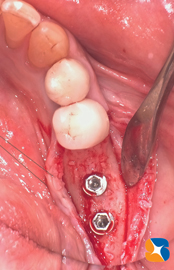

当院では、痛むブリッジを抜歯した日に、インプラント治療に備えて、骨のボリュームを増やす治療を行いました。その際、採血した御自身の血液を使って、左図のCGFとβ-TCP(人工骨)を混ぜ合わせ、抜歯した痕の空洞に添加して、アゴ骨の厚みを増やしておきました。

先日2/7(抜歯&骨の増設治療を済ませてから3ヶ月後)、点滴を使ってインプラントの手術を行いました。骨質は柔らかかったものの、骨の再生は無事に行われていました。